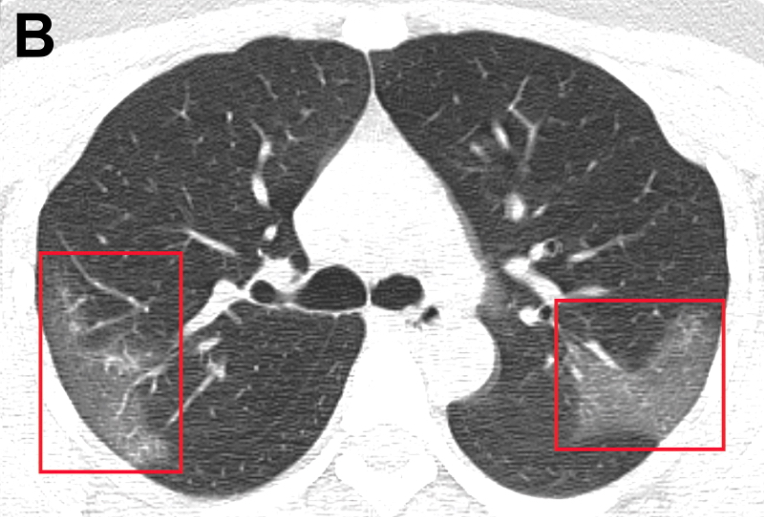

Características clínicas de los pacientes internados con neumonía por 2019-nCoV

Cuadro febril con fatiga y tos seca, evoluciona a disnea en 5 días; presenta linfopenia, LDH elevada y tiempo de protrombina prolongado; tomografía con opacidad bilateral en vidrio esmerilado. El 26% requirió cuidados intensivo y el 4,3% falleció. JAMA, 7 de febrero de 2020